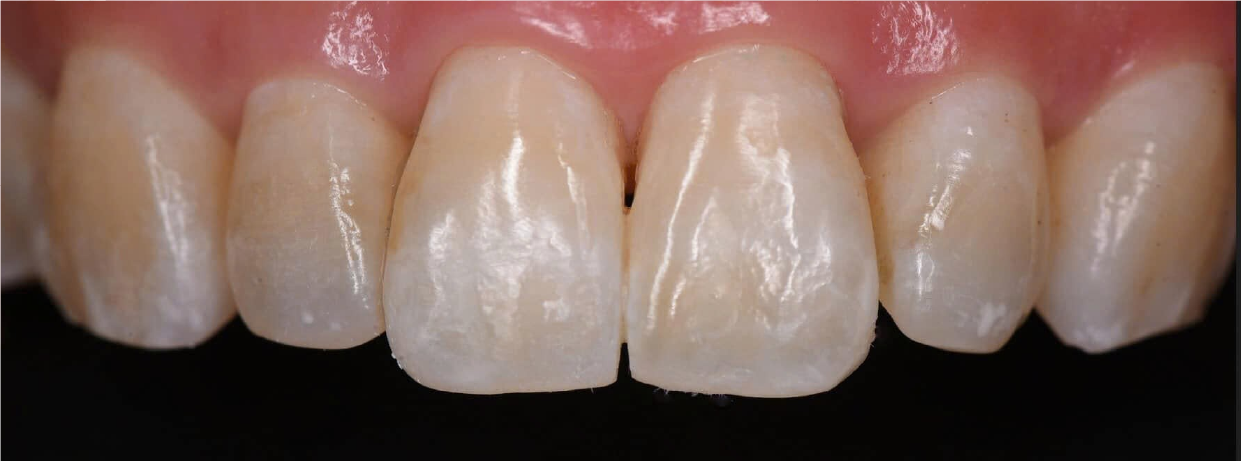

Hình Ảnh Trước & Sau Điều Trị

Minh chứng rõ ràng cho chất lượng và hiệu quả tại Nha khoa Như Ngọc – nơi mỗi khách hàng đều tìm lại được nụ cười tự tin sau quá trình điều trị và thẩm mỹ răng